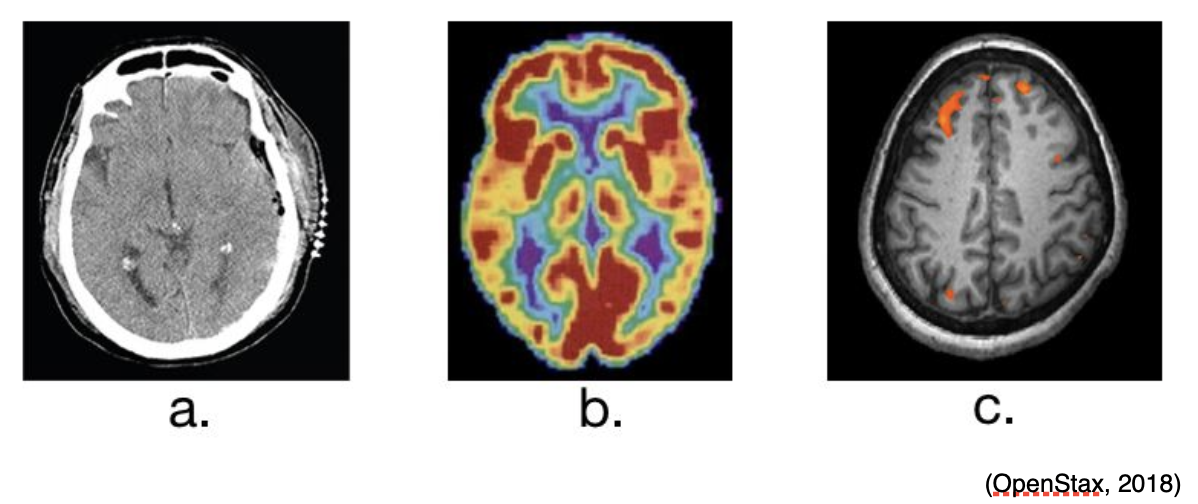

A CT scan can be used to obtain cross-sectional images of the brain to evaluate for structural abnormalities that may be causing the seizures, such as tumors, cysts, or bleeding. A CT scan is a three-dimensional computer-generated image based on x-ray images. An example of an image from a CT scan of the head can be seen below in Figure 2a. Similarly, an MRI can detect lesions or abnormalities in the brain with the use of powerful magnets and radio waves. A more in-depth MRI, called a functional MRI (fMRI), can measure the changes in blood flow within the brain, as seen in Figure 2c. An fMRI may be used prior to surgery to locate critical functions precisely, such as movement or speech, so the surgeon can avoid injury to those areas during surgery. PET scans can be used to detect brain function abnormalities. A small amount of radioactive tracer material is typically injected to help with visualization of chemical activity in certain tissues, as seen in Figure 2b. If the MRI, EEG, or other tests could not determine exactly where the seizures are originating, a single-photon emission CT (SPECT) scan might be conducted. This test uses a radioactive tracer to provide a detailed, three-dimensional map of the blood flow through the brain during seizures (Mayo Clinic, 2019a).

Figure 2

CT (a), PET (b) and fMRI (c) Brain Scan Images